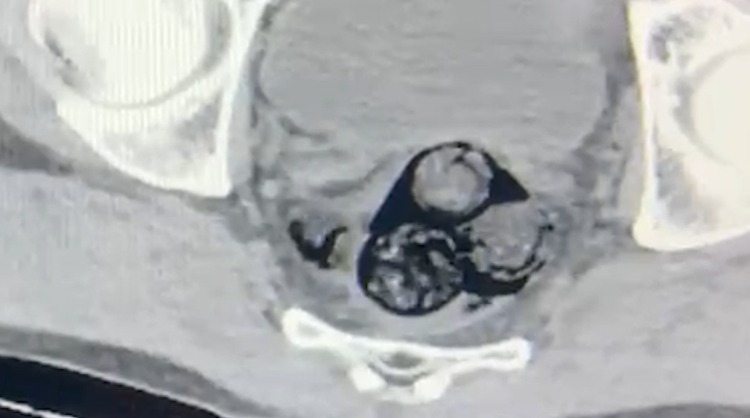

Yapılan detaylı aramalar neticesinde, şahsın vücut boşluklarında uyuşturucu madde taşıdığı belirlendi. Radyolojik görüntüleme sonucu, şüphelinin makat bölgesinde dört farklı yabancı cisim olduğu ortaya çıktı. Sağlık kontrolünden geçirilerek, çıkarılan cisimlerin içinde toplamda 140 gram metamfetamin olduğu tespit edildi. Uyuşturucu madde taşımak ve ticaretini yapmak suçundan hakkında işlem başlatılan A.İ., Iğdır Adliyesi’ne sevk edildi. Mahkemeye çıkarılan şahıs, tutuklanarak cezaevine gönderildi.